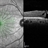

- OCT, macular hole

Optical coherence tomography system

Heidelberg Spectralis - Description

- Optical Coherence Tomography of a 69 year old male with a Macular Hole affecting his right eye. Patient presented at the clinic following visual distortion that had been ongoing for two weeks. Patients vision was Dcc20/200 PHNI. The Physician recommended Pars Plana Vitrectomy/ Membrane Peel Surgery.